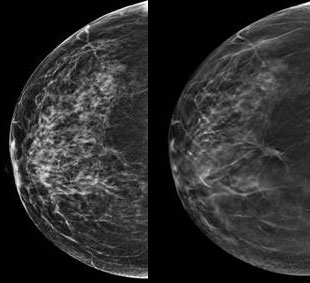

Mammografia trójwymiarowa wykorzystująca zaawansowane techniki obrazowania piersi, określana mianem cyfrowej tomosyntezy piersi, wykrywa znacznie więcej nowotworów piersi niż standardowa mammografia cyfrowa i może potencjalnie zmniejszyć dawkę promieniowania oraz obciążenie związane z badaniami przesiewowymi w kierunku raka piersi - mówią szwedzcy badacze.

W cyfrowej tomosyntezie piersi uzyskuje się quasi-trójwymiarowe obrazy zestawu cienkich plasterków piersi, bez efekt nakładania się, jaki można zaobserwować w standardowej mammografii.